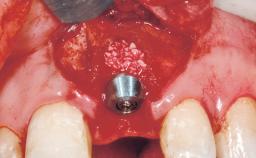

A 30-year-old female patient had lost tooth 21 and was referred to our clinic for consultation and treatment. Due to advanced apical infection, tooth 21 had been extracted two months earlier at another clinic and an acrylic-resin tooth had been bonded to the adjacent teeth. The patient desired implant treatment to avoid any damage to the adjacent natural teeth. While the patient had no history of any systemic disorder, she was a heavy smoker and exhibited medium to advanced periodontitis in the entire jaw. After the initial treatment to achieve a pocket probing depth of less than 4 mm and no bleeding on probing, a decrease in the height of the papillae mesial and distal to the extraction site and overall gingival recession were observed.

Bone Augmentation Horizontal|Staged

Augmentation Materials Autogenous chips|Membrane

Soft Tissue Grafting Simultaneous